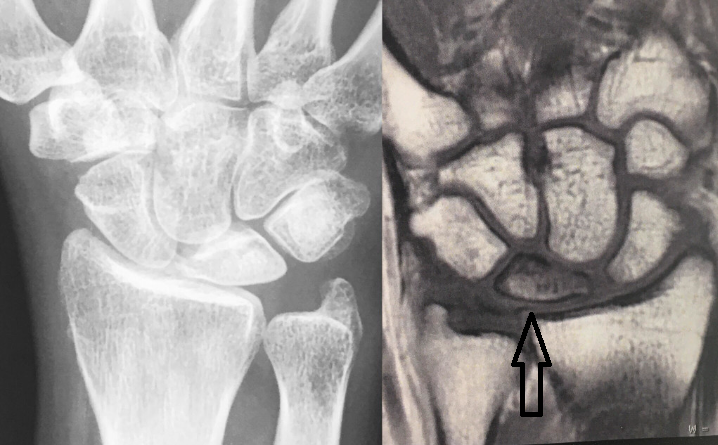

• No RX AP - formato do semilunar → menor e triangular

• No RX AP - altura da ulna → ulna minus

• Ressonância magnética ponderada em T1 → necrose do osso semilunar

• Grau 1 - RX normal // RNM → isquemia, necrose, revascularização

• Grau 2 - RX com esclerose do semilunar